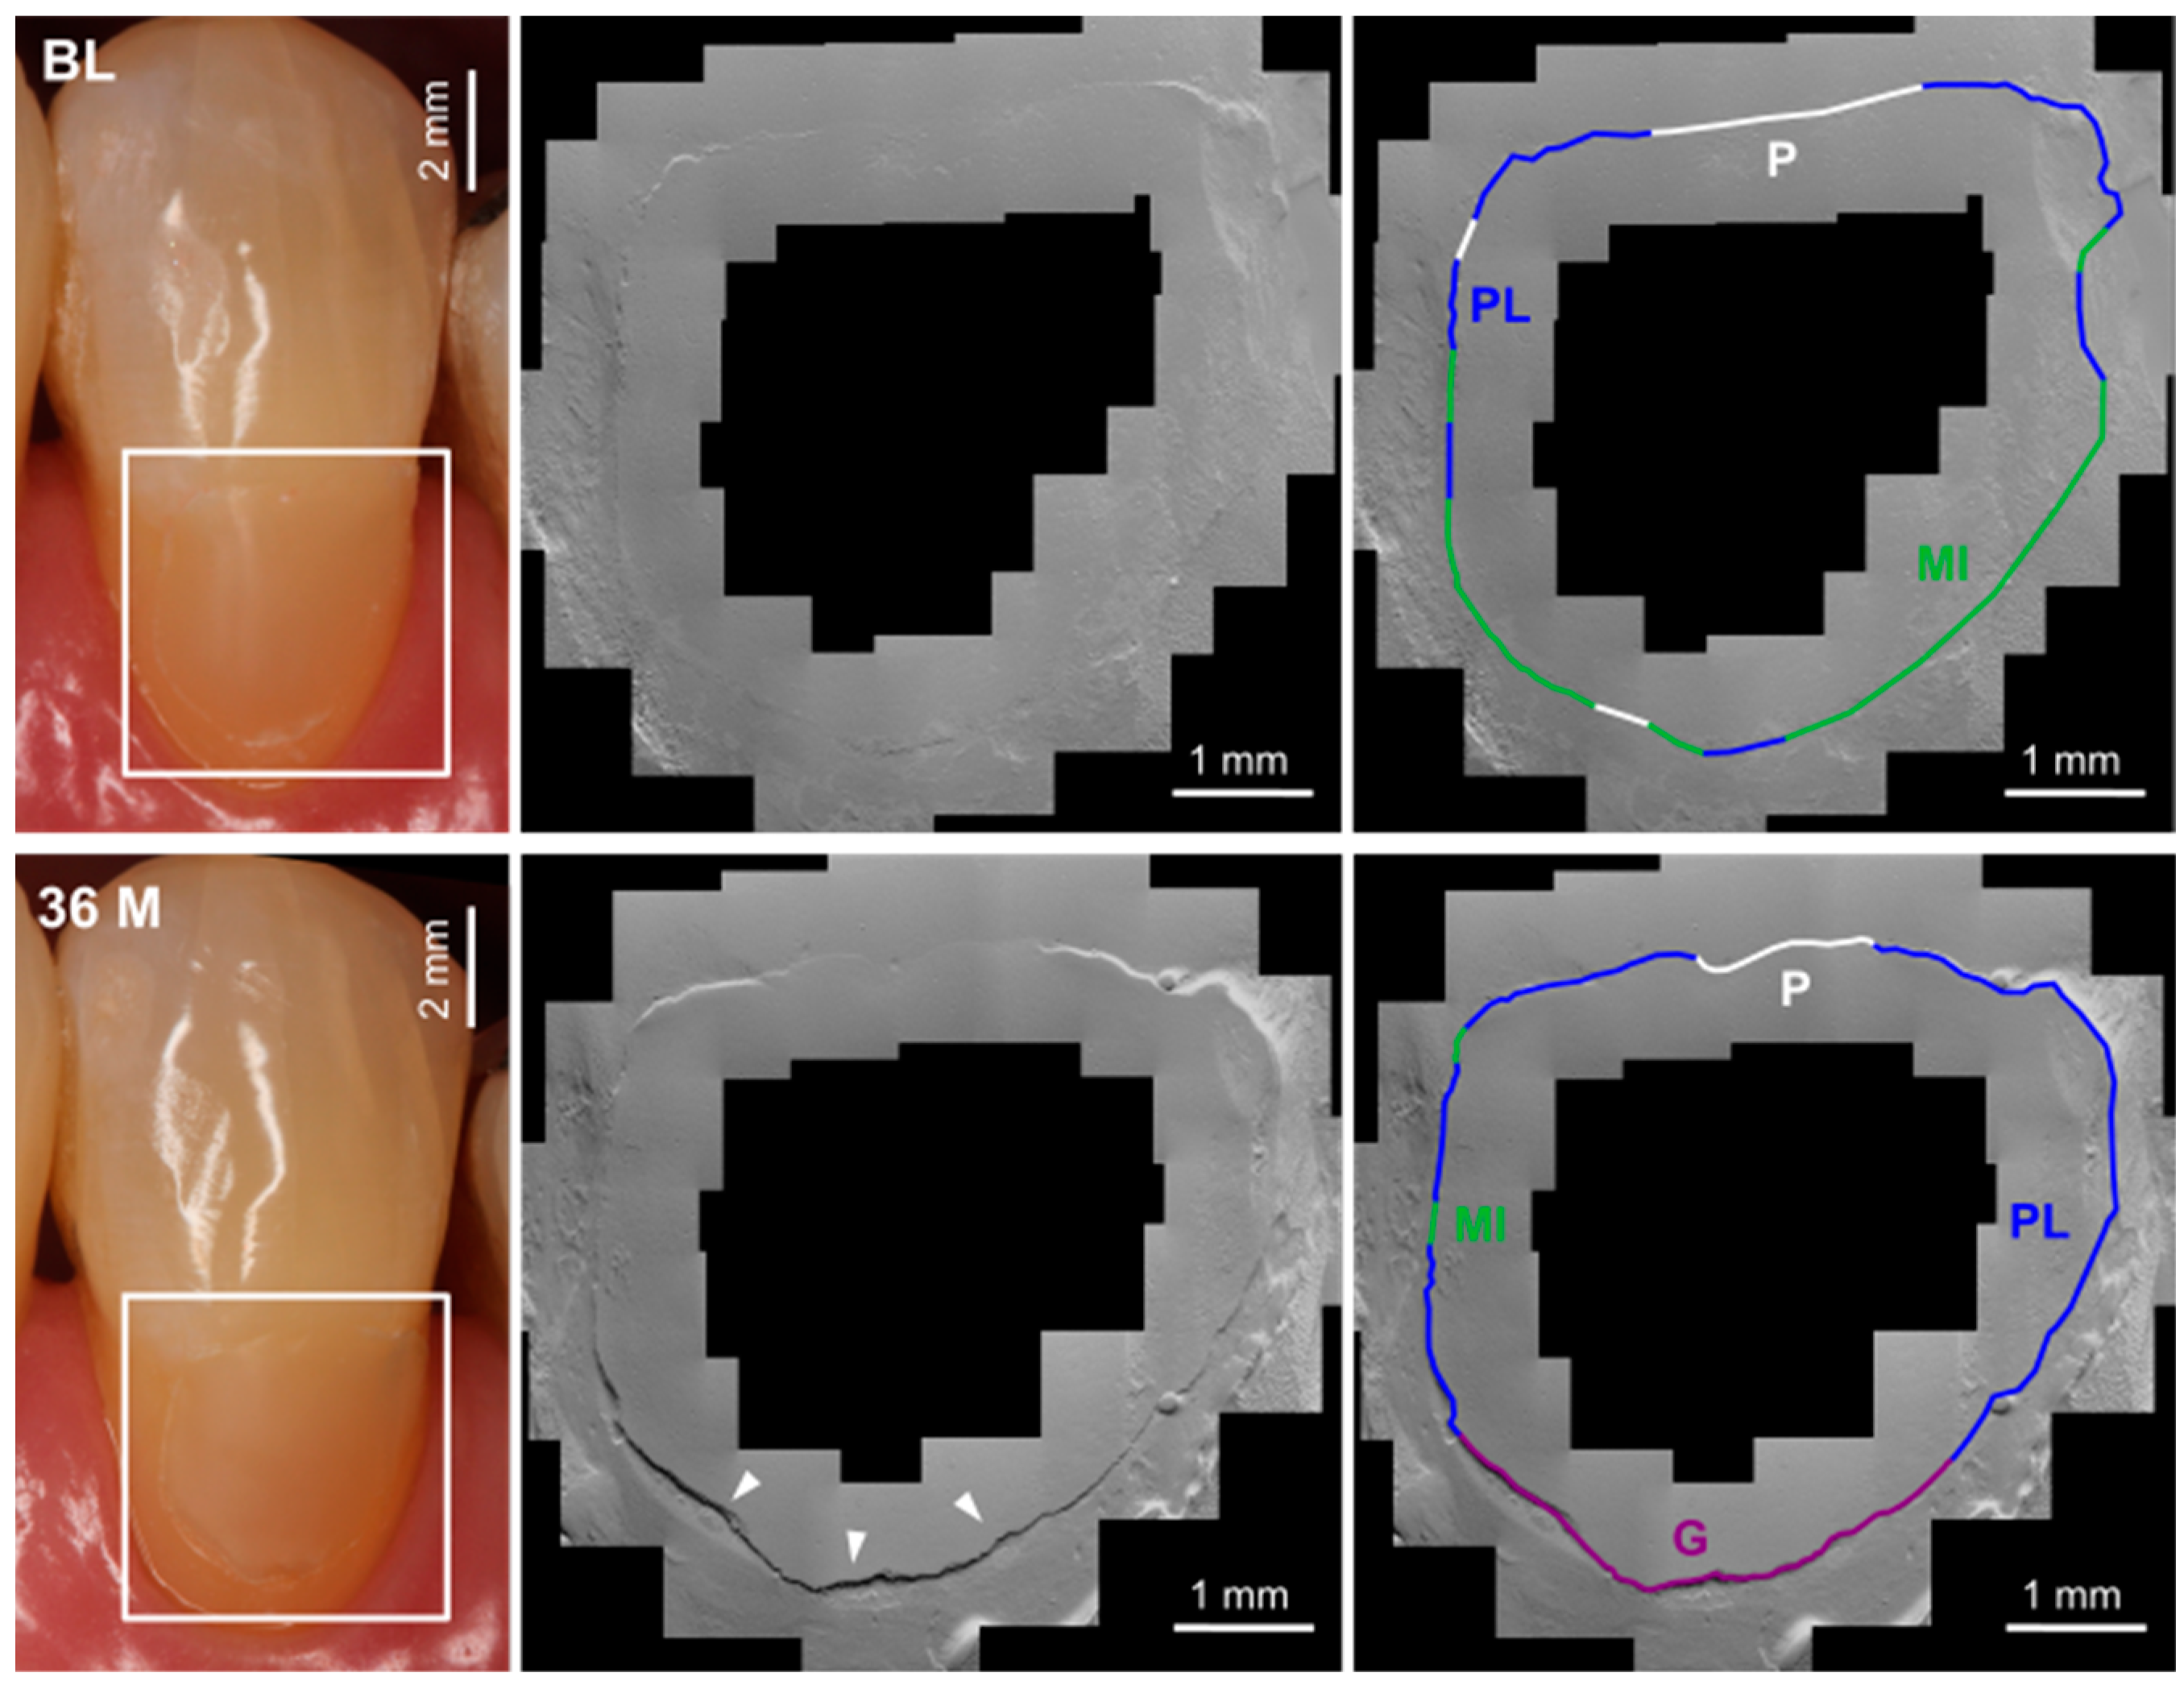

2.5.2. Quantitative Margin Analysis